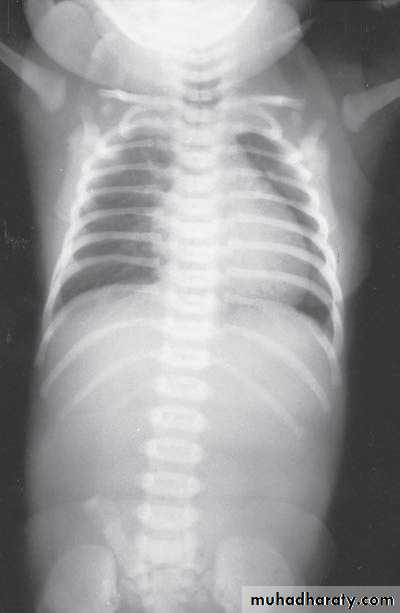

Bowel Obstruction

N.E.C

Meconium ileus+atresia

Hirschprungs disease